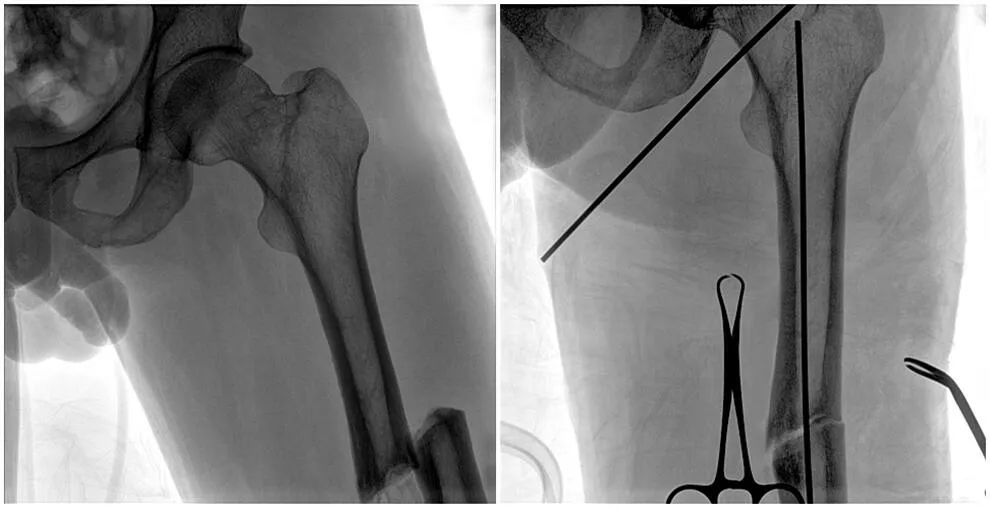

C形臂輔助手術(shù)過程

術(shù)中使用普愛醫(yī)療大平板一體式C形臂進(jìn)行透視,判斷骨折情況及克氏針、髓內(nèi)釘?shù)冉饘僦踩胛锏奈恢?,進(jìn)行調(diào)整。C形臂準(zhǔn)確的術(shù)中定位,大大縮短了手術(shù)的時(shí)間,減輕了患者的痛苦,輔助手術(shù)順利完成。

在進(jìn)行髓內(nèi)釘內(nèi)固定術(shù)時(shí),醫(yī)生需要同時(shí)觀察到入釘點(diǎn)和骨折部位的情況,普愛醫(yī)療大平板一體式C形臂采用30CM×30CM的平板探測器,能夠呈現(xiàn)更廣闊的成像面積,滿足大部分長骨髓內(nèi)釘內(nèi)固定術(shù)的攝片需求。

術(shù)中定位準(zhǔn)確、出血量少,術(shù)后影像顯示股骨移位糾正,恢復(fù)良好力線,手術(shù)效果良好。